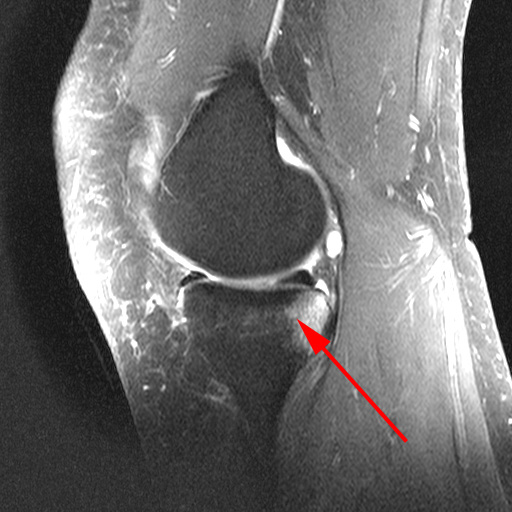

Knæ, Bone-Bruise, MR 1

MR-skanning af knæet der viser småfrakturer i trabeklerne (bone bruise) hos to forskellige patienter. Denne slags småfrakturer er ikke synlige på en almindelig røntgenoptagelse.